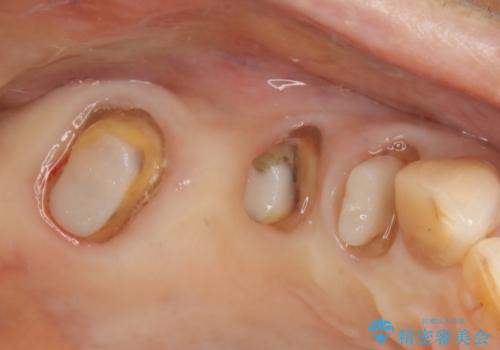

- 数十年前、アメリカで行った治療部位のやり直しを希望されてご来院。

ツギハギの修復が行われてきた被せ物は、縁が合っておらず隙間があり見た目も悪くなってしまっていました。

古い被せ物を除去し、中の状態をキレイにしたうえで改めて金属を使用していない被せ物で噛み合わせの回復を行いました。

被せ物の色は噛み合う反対側の被せ物と合わせて作りました。